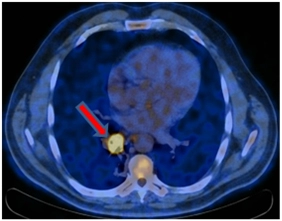

ПЭТ-КТ от 12.01.2017. В правом легком определяется мягкотканое образование метаболическим размером 30×24 мм с кальцинатом в структуре SUVmax=21,36, перекрывающий просвет промежуточного бронха справа сразу за уровнем ответвления среднедолевого бронха с формированием картины «культи бронха» – в бифуркационном лимфатическом узле до 20 мм SUVmax=4,77.

Стадирование. T1bN2M0 StIIIa.